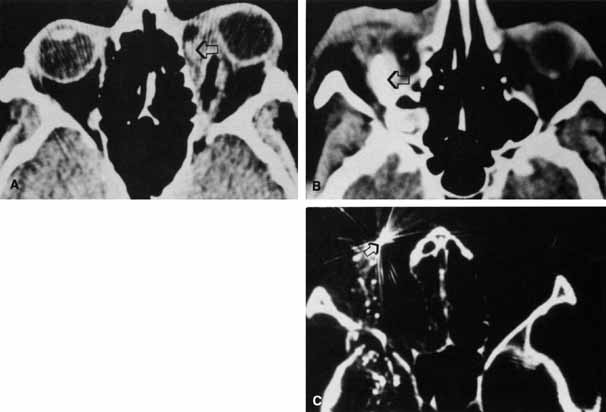

Hemorrhage can be localized to the subperiosteal potential space, extraconally, or intraconally within the orbital soft tissue, or within the belly of extraocular muscles. The condition can be associated with pain, nausea, diplopia, or decreased vision. The more obvious finding might be lid ecchymosis and edema but requires further examination for retroseptal signs. There may be conjunctival chemosis or expanding ecchymosis. Clinical findings reflect the mass effect of accumulating blood within the confines of the bony orbit and orbital septum (Fig. 2). Subperiosteal hematomas are usually restricted by the tight adherence of the periosteum to the orbital bone except in areas, such as suture sites, where this association is weakest. Hemorrhage localized to the muscle sheath may cause selective extraocular muscle restriction that requires radiologic studies to distinguish it from incarceration into a fracture site (Fig. 3). Localized bleeds within the orbital soft tissue can produce proptosis or dystopia. Diffuse hemorrhage may limit eye movement globally and increase retropulsive resistance. Increased intraorbital pressure on the globe and optic nerve may cause elevated intraocular pressure, choroidal folds, compressive retinal vascular compromise, or optic neuropathy, so maintaining vigilance for progressive, potential, vision-threatening situations is important.

Fig. 2 Proptosis, ecchymosis, and chemosis resulting from orbital hemorrhage.

Fig. 3 CT scan of inferior orbital hematoma (X) involving the inferior rectus muscle and causing severe upgaze and moderate downgaze limitation.